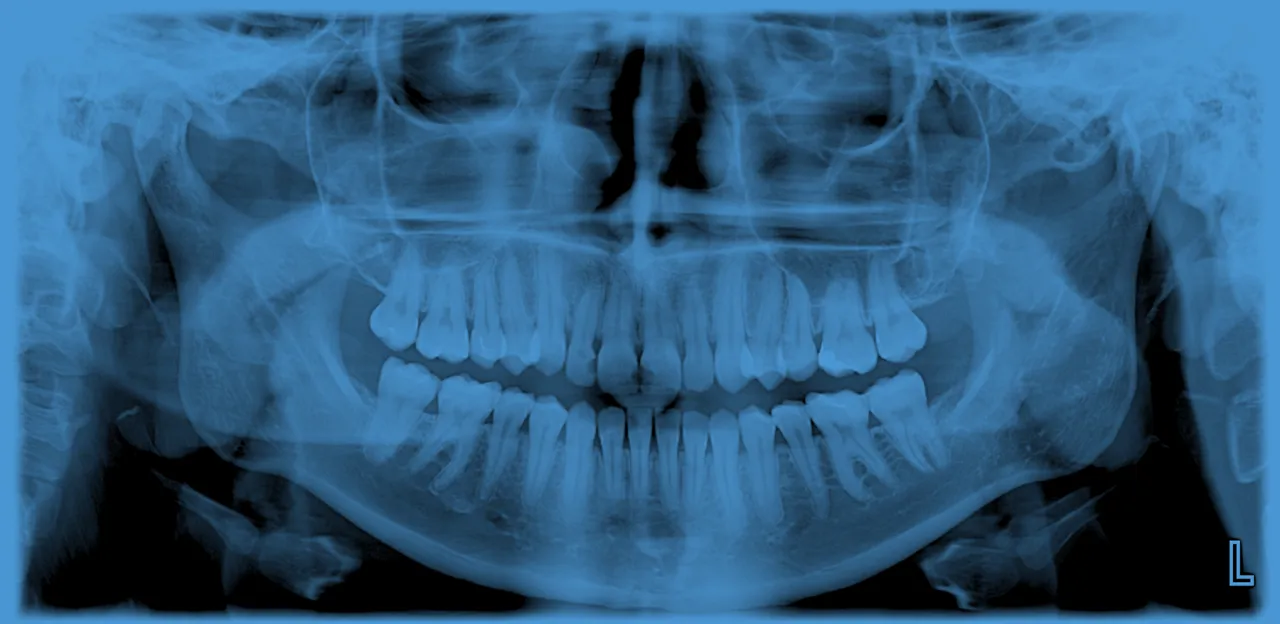

- Pantomogram to przeglądowe zdjęcie rentgenowskie, które ukazuje wszystkie zęby, kości szczęki i żuchwy, stawy skroniowo-żuchwowe oraz częściowo zatoki szczękowe.

Zdjęcie panoramiczne, znane szerzej jako pantomogram, to podstawowe, przeglądowe badanie radiologiczne w stomatologii. Jego głównym zadaniem jest przedstawienie ogólnego stanu całej jamy ustnej na jednej kliszy. Obejmuje ono nie tylko wszystkie zęby zarówno korony, jak i ich korzenie ale także kości szczęki i żuchwy, stawy skroniowo-żuchwowe, a nawet fragmenty zatok szczękowych i nosa. Dla mnie, jako dla stomatologa, to narzędzie jest absolutnie kluczowe, ponieważ daje mi pełny obraz sytuacji i pozwala na kompleksową ocenę stanu zdrowia pacjenta, co jest fundamentem każdej skutecznej terapii.

Kiedy patrzę na pantomogram, widzę znacznie więcej niż tylko zęby. To prawdziwa mapa, która ukazuje wzajemne relacje między różnymi strukturami anatomicznymi. Pozwala mi to na holistyczną ocenę zdrowia jamy ustnej i okolicznych rejonów.

Zęby od korony po wierzchołek korzenia: ocena stanu uzębienia

Na pantomogramie doskonale widać wszystkie zęby zarówno te wyrznięte, jak i te, które dopiero czekają na swoją kolej, czyli zawiązki zębów. Mogę ocenić kształt i długość korzeni, obecność ewentualnych zmian okołowierzchołkowych, a także wychwycić nieprawidłowości w budowie, takie jak zęby nadliczbowe czy brak zawiązków. To badanie jest niezastąpione, gdy chcę sprawdzić, czy wszystkie zęby rozwijają się prawidłowo i czy nie ma żadnych ukrytych problemów z ich strukturą.

Kości szczęki i żuchwy: fundament Twojego uśmiechu pod lupą

Kości szczęki i żuchwy to fundament, na którym opiera się cały Twój uśmiech. Pantomogram pozwala mi ocenić ich gęstość, strukturę i ogólny stan. Mogę wykryć obszary zaniku kości, co jest kluczowe w diagnostyce paradontozy, a także zidentyfikować inne zmiany patologiczne, takie jak torbiele czy guzy, które rozwijają się w obrębie tkanki kostnej. To niezwykle ważne, ponieważ zdrowe kości są podstawą dla stabilnych zębów i przyszłych uzupełnień protetycznych.

Stawy skroniowo-żuchwowe: klucz do komfortowego gryzienia

Często pacjenci są zaskoczeni, że na zdjęciu zębów widać również stawy skroniowo-żuchwowe (SSŻ). Ich ocena jest jednak niezwykle ważna. Problemy z SSŻ mogą prowadzić do bólu, trudności w otwieraniu ust czy nieprzyjemnych "kliknięć" podczas jedzenia. Na pantomogramie mogę dostrzec zmiany w strukturze stawów, które mogą być przyczyną dyskomfortu i pomóc w skierowaniu pacjenta na dalszą, bardziej szczegółową diagnostykę, jeśli zajdzie taka potrzeba.

Zatoki szczękowe i nos: co zdjęcie zębów mówi o Twoim zdrowiu ogólnym?

Pantomogram, choć skupia się na jamie ustnej, częściowo ukazuje również zatoki szczękowe oraz dolne partie nosa. To pozwala mi na wstępną ocenę ich stanu. Czasem na zdjęciu widoczne są zmiany zapalne, zgrubienia błony śluzowej czy obecność ciał obcych w zatokach. Oczywiście, nie jest to badanie dedykowane laryngologii, ale może wskazać na potrzebę konsultacji z innym specjalistą i jest cennym uzupełnieniem ogólnej oceny stanu zdrowia pacjenta.